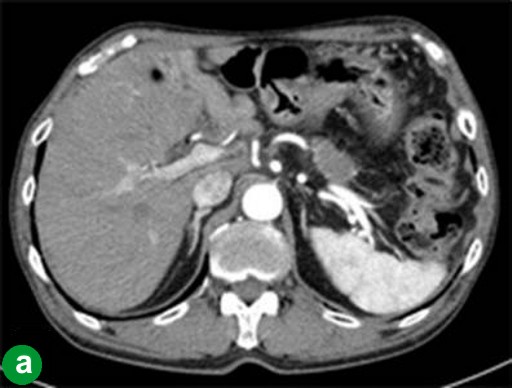

In March 2008 (28 months after the initial operation), the CA 19-9 level increased to 44 U/mL (reference range: 0-36 U/mL). An abdominal CT scan revealed a low density lesion at the cut end of the pancreas (Figure 4a), and this region appeared as a hot spot on FDG-PET (Figure 4b). A remnant proximal pancreatectomy with duodenectomy was performed in August 2008. Histopathological examination of the second neoplasm confirmed a moderately- to poorly- differentiated adenocarcinoma which were different than the findings in the initial neoplasm (Figure 4c). The second findings led to a diagnosis of a metachronous pancreatic carcinoma with vessel, lymph duct and neuron invasion accompanied by lymph node metastases (T3N1M0; R0; pathological stage: IIB). The patient showed multiple liver metastases 8 months after the second operation.

Figure 4. Case#2: second operation. a. Abdominal CT revealed a low-density lesion at the cut end of the pancreatic head. b. FDG-PET showed a hot spot at the same pancreas head location as the tumor appeared on CT. c. Moderately differentiated tubular adenocarcinoma. The cancer cells invaded as a tubular and/or papillary structure. (H&E stain, x100). |